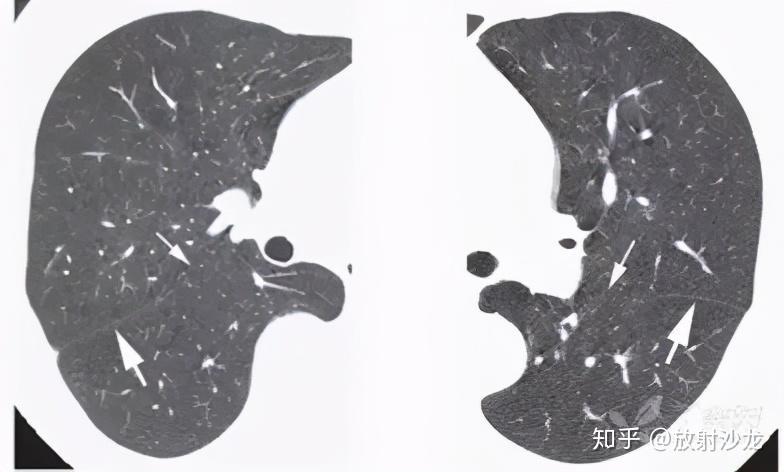

这例叶间裂下坠征象真的是肺炎克雷伯杆菌感染引起的吗

右侧叶间裂少量包裹性积液.女,78岁,因反复患肺炎多次住院治疗.